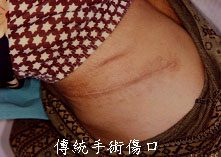

PCNL於1976年由Fernstrom與Johannson完成首例,到1980年早期已是一趨近成熟的手術。傳統的手術方式是讓病患趴臥在手術檯上,胸腹部以枕頭墊高,使側腹得以向上突起,由X光透視結石的位置,在背部做腎臟穿刺。首先以穿刺針穿刺,經皮膚、腎臟皮質,通到腎盞內,先留置一條.035或.038的導線,再沿著導線以擴張管(Fascial dilator)將此腎臟通道擴張至24~30F,接著放置安氏套管(Amplatz sheath)當工作通道,方便腎臟鏡進出腎臟,將腎結石以水電波導線(electrohydraulic probe)、超音波碎石棒(ultrasonic lithotriptor)或震動碎石棒(lithoclast)擊碎,再以取石鉗(Forceps or basket)取出。手術結束前通常會在輸尿管及腎臟通道分別留置一條輸尿管導管及一條腎造瘻管,身體外表只有一個一公分左右的傷口。術後48小時拔除腎造瘻管即可準備出院,腎造瘻管拔除後遺留下的傷口會暫時滲尿,但24小時內通常會自行癒合。這種手術方式住院時間約在五天以內,比腎臟半切取石手術的方法輕鬆,而且對腎臟極少傷害。

但是這種傳統的PCNL方式,具有先天上的重大缺點。1.病人需變換姿勢成趴臥,若搬動不小心,容易意外造成關節扭傷,且浪費手術時間。2.病人趴臥,對呼吸、血液循環都有不利的影響︰麻醉方面比較危險,而且頭常需側向一邊,容易妨礙腦部血液循環。3.病人趴臥,由背部做腎臟穿刺,經由腰背肌肉時,不只手術當中的器械操作較不靈活,結石碎塊較不易清除乾淨,也較容易流血。4.因解剖位置的關係,腎臟通道的角度通常有較大的仰角,手術的醫師常需站立完成手術,若手術時間長,體力的損耗也大。5.以放射線X光透視定位,增加醫師及病人輻射曝露的機會,其效應往往是數年後才發現,有可能導致皮膚發紅、毛髮脫落、白內障、不孕、體內血液細胞的變化,甚至癌化或基因突變。6.手術後有些病人會抱怨胸部趴臥處不適。

此項手術技巧,不只針對大的腎結石或輸尿管結石,其它如腎水腫、腎盂輸尿管狹窄或腎臟腫瘤等疾病,配合新近推出的軟式腎臟鏡及軟式輸尿管鏡,在泌尿系統疾病的診斷與治療上都有更寬廣的應用及非凡的價值。甚至有小至一公分左右的腎結石,位於腎盞憩室內,經數次體外震波碎石術擊碎,但仍無法排出結石的病患,亦經由此方法而順利完成手術。因此,這種結合平躺姿勢,應用超音波定位技術的經皮腎造瘻截石手術,可減少病人翻身的麻煩及危險,節省寶貴的手術時間,避免腸穿孔等重大併發症,減少輻射曝露,手術傷口小、效果佳、恢復快,是一種極為安全及方便的手術方式,預料未來伴隨相關診斷與治療儀器的推陳出新,這種手術技巧將有更大的應用空間。